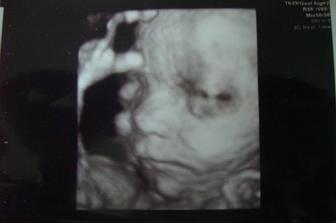

sofi

24. dec 2008

Jaruško 2

Moje druhé Vianoce